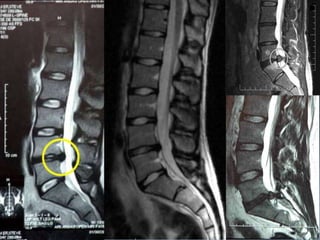

RX TC RMI

74% das RMI possuem anormalidade(s) sem dor!

(Jensen et al., 1994)

Protrusão

Hénia extrusa ou prolapso discal

Sequestro

(Adams et al., 2002)